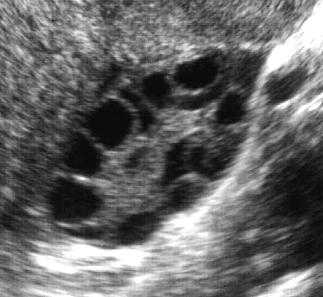

Синдром поликистозных яичников (СПКЯ) – это патологическое состояние яичников, сопровождающееся нарушением гормонального баланса и часто ожирением, а также бесплодием. Встречается у 15% женщин репродуктивного возраста, считающих себя здоровыми и не предъявляющих соответствующих жалоб ( возможная скрытая форма). Около 80 % женщин, предъявляющих жалобы на чрезмерное оволосение и аменорею, страдают СПКЯ.

В норме каждый месяц у женщины репродуктивного возраста происходит овуляция. Под действием, так называемого, ФСГ (фолликулостимулирующего гормона) в середине цикла яйцеклетка выходит из яичника и поглощается маточными трубами, где должно произойти оплодотворение. В гипофизе (эндокринный центр мозга) одновременно с ФСГ синтезируется и ЛГ (лютеинизирующий гормон). ЛГ, в свою очередь, отвечает за выработку половых гормонов (эстрогенов и прогестерона). Поликистозные яичники развиваются по причине того, что в гипофизе женщины вырабатывается преимущественно ЛГ, таким образом, количество ФСГ уменьшается. Как мы помним, ФСГ отвечает за овуляцию, значит, при СПКЯ овуляции не происходит. Фолликул остаётся в яичнике. В это время клетки фолликула синтезируют жидкость, этой жидкостью заполняется полость созревшей яйцеклетки, и образуется киста (полость, заполненная жидкостью). Таких кист с каждым циклом становится всё больше и больше. Причиной развития синдрома поликистозных яичников (СПКЯ) могут стать осложнённая беременность, аборты, стрессы, инфекции, интоксикации, когда нарушается сбалансированная выработка ЛГ и ФСГ. Помимо СПКЯ, известна болезнь поликистозных яичников (БПКЯ), в основе которой лежат генетические изменения. То есть это наследственное заболевание. Первые симптомы заболевания проявляются в пубертатном возрасте, когда у девочки идёт процесс становления цикла. Толчком к развитию БПКЯ могут быть пережитые в этот период сильный стресс, инфекция, интоксикация (алкоголь, табак, курение, неправильное питание), которые навсегда могут оставить девочку бесплодной либо привязать к приёму дорогостоящих препаратов.